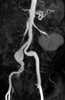

Normal iliac artery

The common iliac arteries are two large arteries that originate from the aortic bifurcation at the level of the fourth lumbar vertebra. They end in front of the sacroiliac joint, one on either side, and each bifurcates into the external and internal iliac arteries. [Source: Wikipedia ]